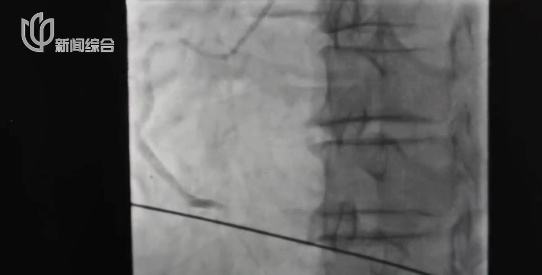

检查结果显示,郭先生心脏右冠状动脉远段已经完全闭塞,没有任何血流通过。

他远端这根血管所供应到的心肌,就它的下游,完全就是堵掉了。

医生立即为郭先生置入心梗支架

这才稳定了病情